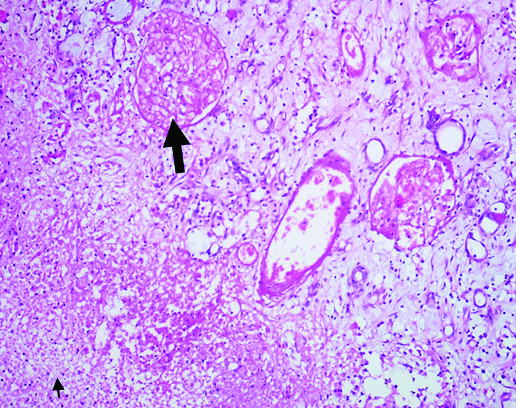

On gross examination left kidney weighed 480 gram and measured 14×9×7 cm3. Outer surface showed large areas of haemorrhage and necrosis. Cut surface showed patchy areas of haemorrhage and necrosis in the cortex and medulla [Table/Fig-2]. Microscopy showed extensive corticomedullary necrosis, focal haemorrhage and overlying marked infiltration with neutrophils, cell debris, few foamy macrophages and lymphocytes in the parenchyma [Table/Fig-3]. There were very few viable glomeruli that showed mild mesangial prominence with fairly open capillary lumina lined by membranes of normal thickness. Bowman capsules were unremarkable. Tubules revealed mild degenerative changes. Interstitium was mildly prominent for focal oedema and leucocytic infiltration. Blood vessels were unremarkable. She was discharged two weeks after surgery. On follow up of three months she had no complaints and is on anti-retroviral therapy.

Cortical necrosis (↑) focal hemorrhage and overlying marked infiltration with neutrophils, cell debris and lymphocytes (↑) (H&E, x100).